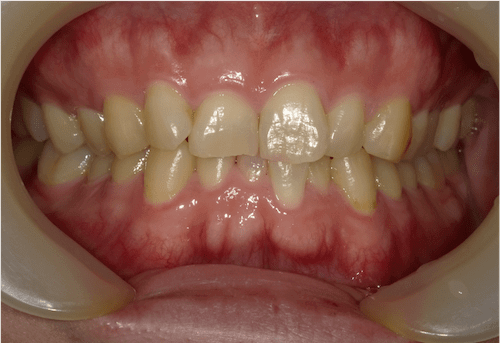

軽度の叢生

BEFORE

AFTER

担当医コメント

上下顎に軽度の叢生があった。奥歯の位置を調整し左上の前歯の捻転を含めて、インビザラインでの改善が可能と判断し、治療をすすめました。

治療の概要

年齢/性別

42歳 女性

主訴

前歯の位置が気になる

リスク

歯肉退縮が起こる可能性がある。

費用

82万円(矯正費用)

期間

8ヶ月